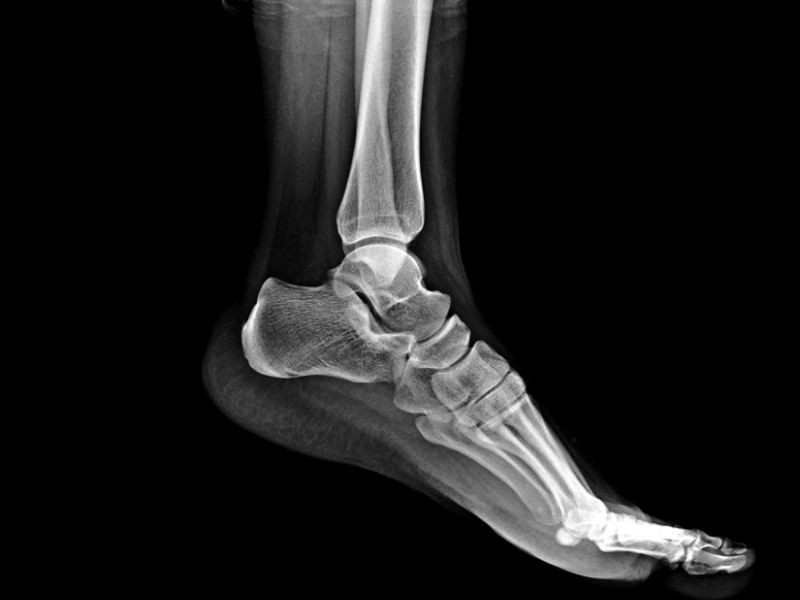

Doktorunuz ayak bileği ekleminizin birkaç filmini isteyebilir. Doktorunuzun incinen ve incinmeyen eklemleri karşılaştırabilmesi için diğer ayak bileğinizin filmine de ihtiyacı olacaktır. Bazı vakalarda kemik taraması, komputed tomografi(CT) ve manyetik rezonans görüntüsü (MRI) gibi ilave edilen testlere ihtiyaç olabilir.